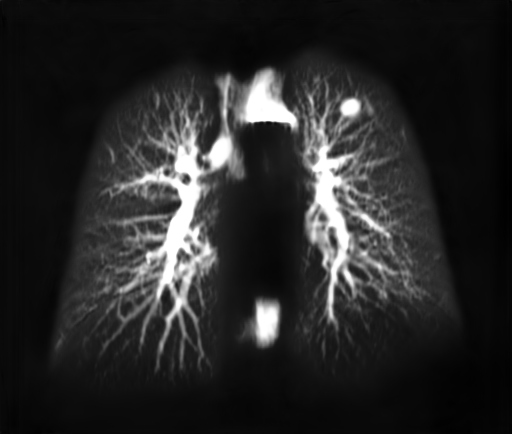

2.3 Lung Structures Extraction Method

The input to the lung structures extraction algorithm is a synthetic X-ray. The output is an image which includes only the lung structures appearing in the original image. In order to teach a FCNN to perform this decomposition task, we make use of the 3D CT data. A DRR of the lungs which we term “Lung X-ray” is created and used as the training target image. Training pairs of source and target images are generated as detailed next:

2.3.2 Target “Lung X-ray” image Generation:

Utilizing the 3D segmentation map Mlungsubscript𝑀𝑙𝑢𝑛𝑔M_{lung}, we mask out all non Lung voxels yielding GLungsubscript𝐺𝐿𝑢𝑛𝑔G_{Lung}.

GLung=MlungG(x,y,z)subscript𝐺𝐿𝑢𝑛𝑔subscript𝑀𝑙𝑢𝑛𝑔𝐺𝑥𝑦𝑧G_{Lung}=M_{lung}\cdot G(x,y,z) (4)

A DRR can now be generated as before for GLungsubscript𝐺𝐿𝑢𝑛𝑔G_{Lung} using Eq.3. As a consequence, the DRR generation process is now limited to the lung area. An example result of the “Lung X-ray” generation process is given in Fig.4. It is noticeable that only inner lung structures appear, excluding overlapping anatomical structures.

Refer to caption

(a)

(b)

Figure 4: (a) DRR Source Image: (b) “Lung X-ray” Target Image for Training